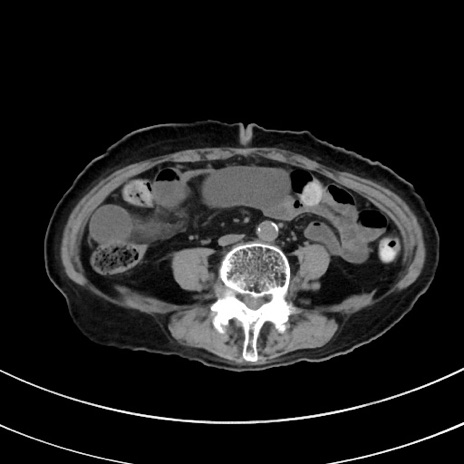

症例33(横断像)

冠状断像

【症例】70歳代 女性

【主訴】心窩部痛

【現病歴】延髄病変の精査・加療にて神経内科入院中。本日より心窩部痛あり。

【身体所見】右下腹部を中心に圧痛と反跳痛あり。

【データ】WBC 10900、CRP 0.02